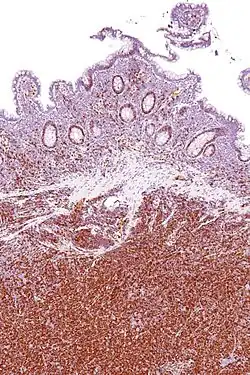

Micrograph of cyclin D1 staining in a mantle cell lymphoma

Immunohistochemical staining of cyclin D1 antibodies is used to diagnose mantle cell lymphoma.